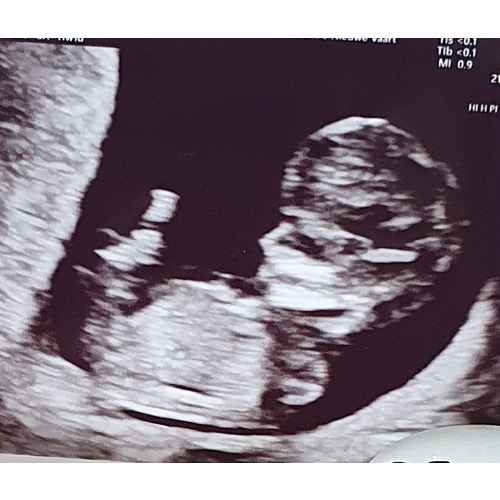

Kleintje van ons heeft ook een groot hoofdje, althans vind ik...., echo was met 10,5

Als ik in de verschillende baby apps kijk, zie ik sowieso dat foetussen normaal in de eerste weken een groot voorhoofd hebben.

Het is heel normaal dat het hoofdje zo groot is. Mij is uitgelegd dat het hoofdje van de foetus tot week 12 groter is dan het lijfje zelf. Na week 12 zal het gaan vormen naar hoofdje wat je foetus dan krijgt.

Ik heb net gelezen dat de hersenen sneller groeien als de rest en het Darom in vergelijking van de rest van zijn lichaam een groter hoofd heeft.